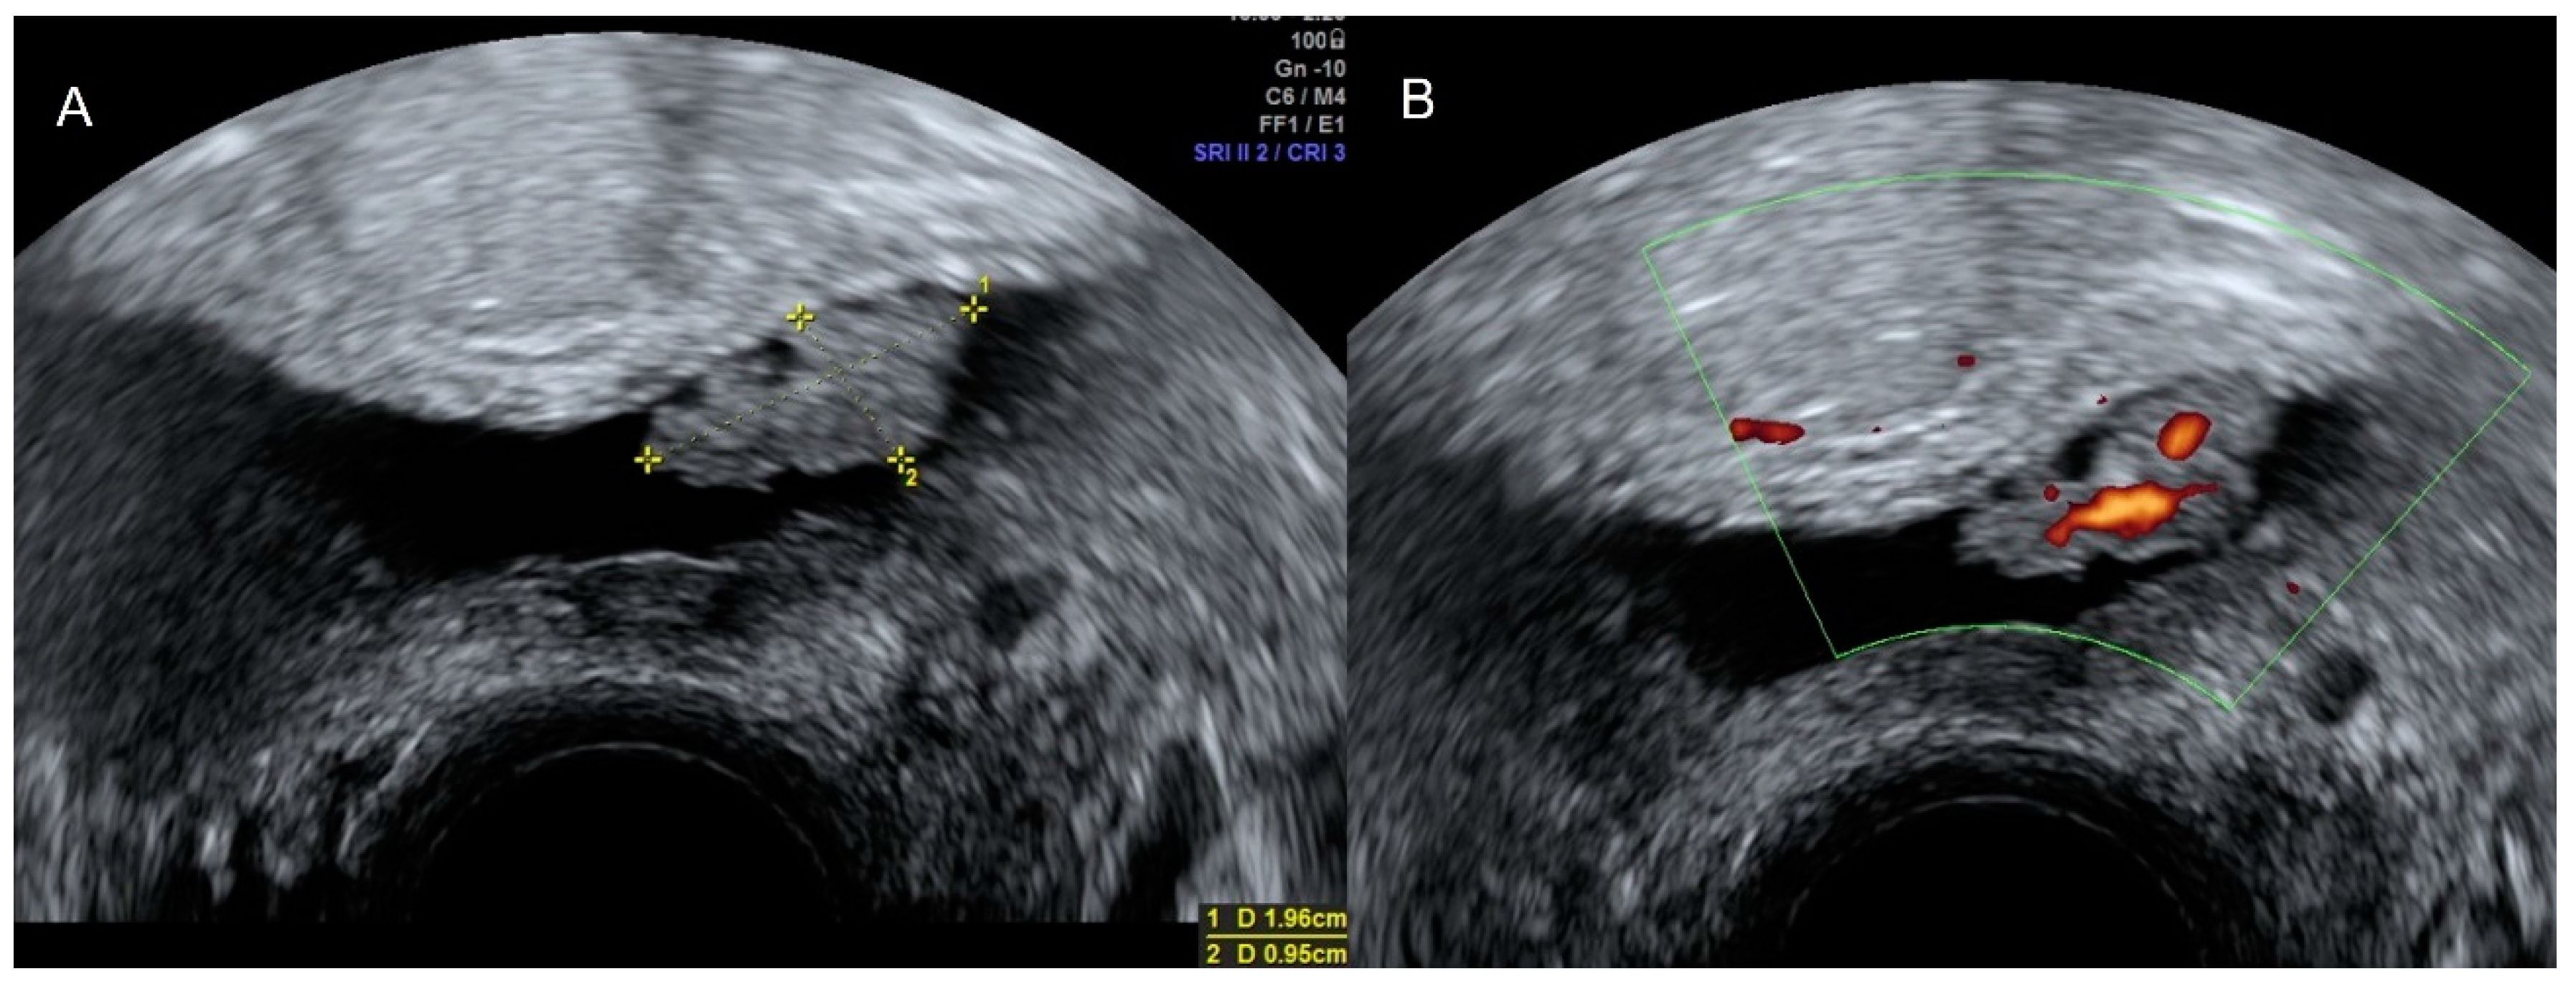

3.2. Benign and Malignant Bladder Pathology